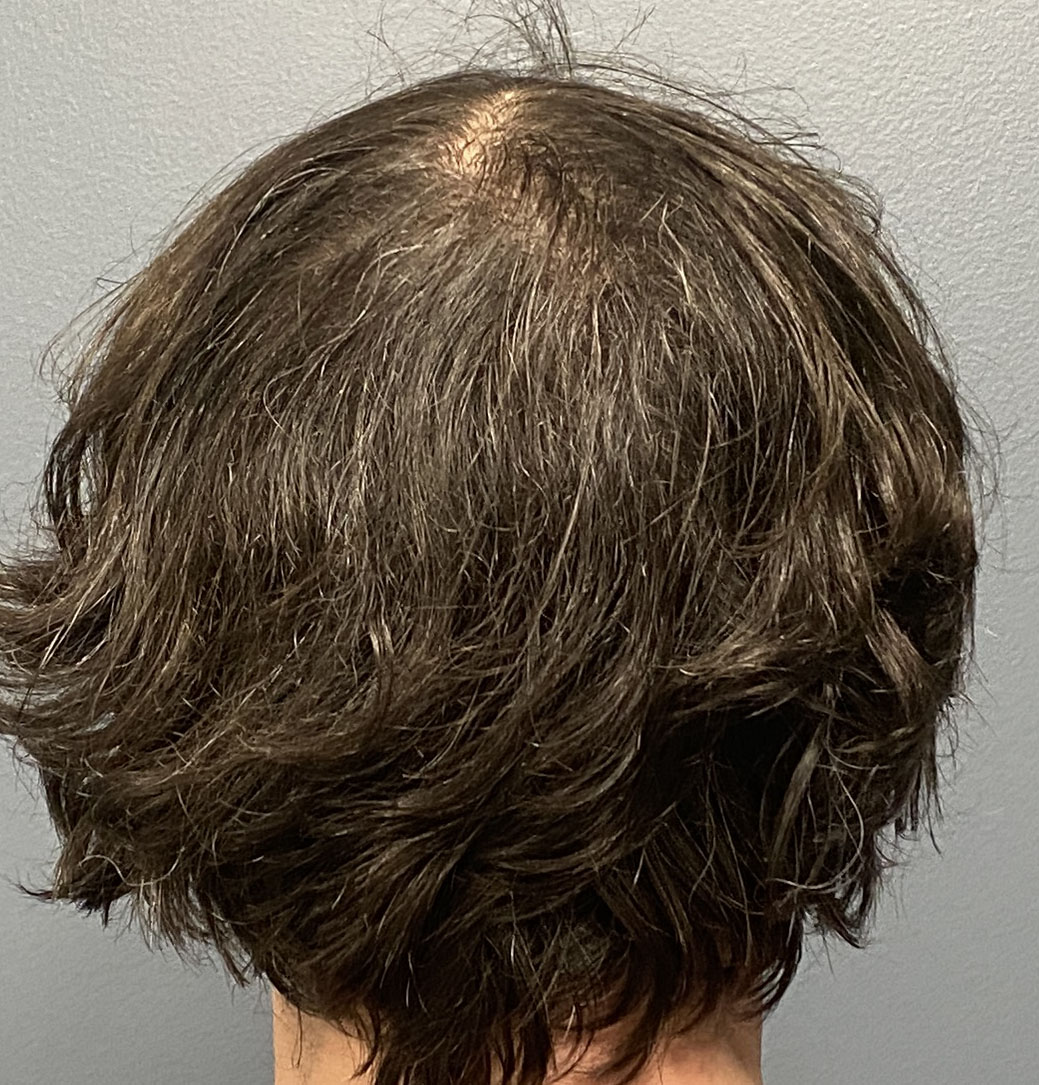

Patient 45

Desire for reduction in height of top of head.

Top of head skull reduction by removal of the outer cortical bone layered by a grid burring technique.

Desire for reduction in height of top of head.

Top of head skull reduction by removal of the outer cortical bone layered by a grid burring technique.